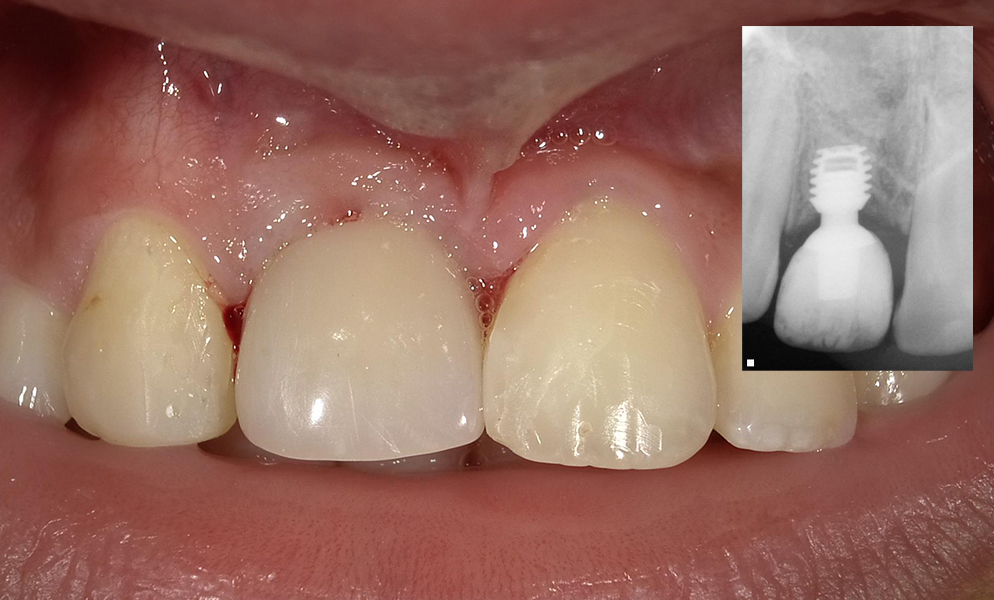

| Before | After |

![]() |

| Single anterior tooth missing space restored with a short dental implant (Bicon, USA) | |